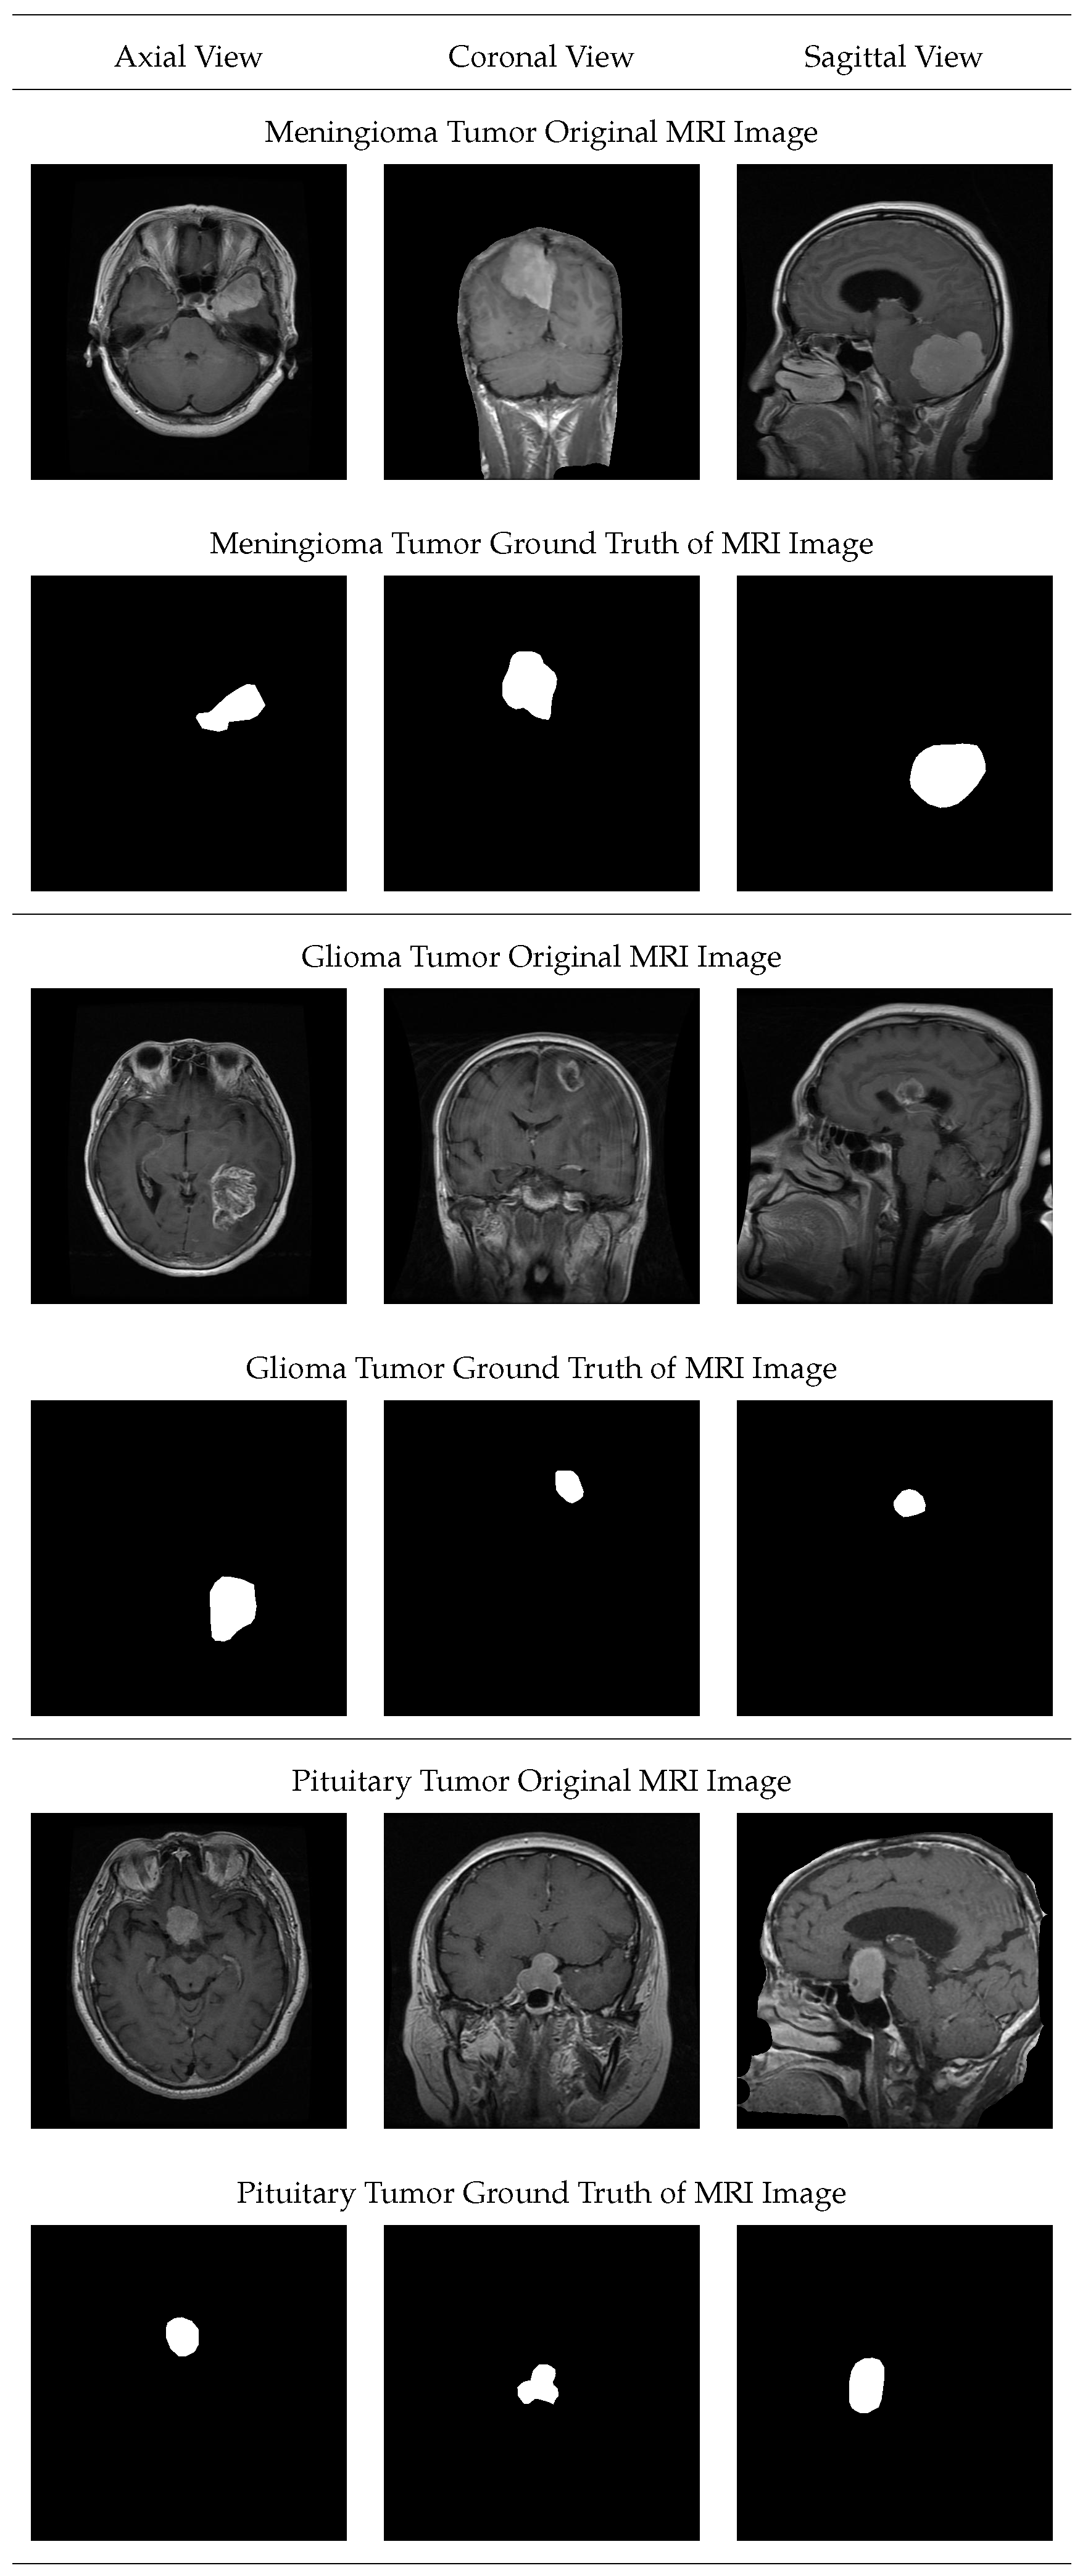

4. Dataset Description

5.2. Analysis of Proposed Hybrid Segmentation Approach for the Brain Images